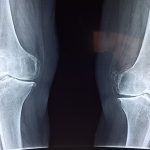

Rodilla hinchada o agua de rodilla, líquido en la articulación

El exceso de líquido acumulado en la articulación de la rodilla o su alrededor, ocasiona una rodilla hinchada.  También es llamado en el campo médico...